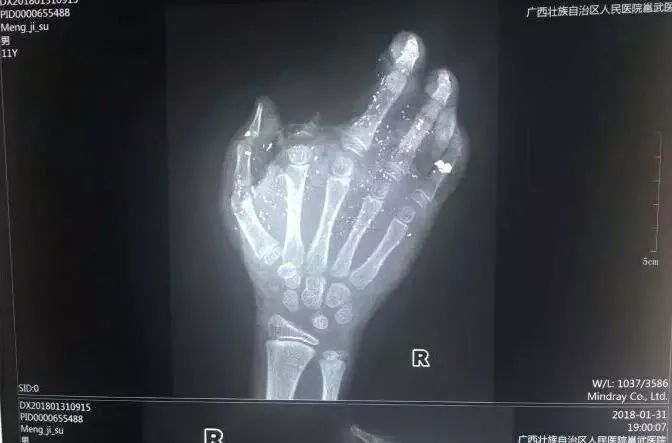

手機(jī)爆炸致男孩手掌被炸傷

2018年1月31日,

廣西也發(fā)生過一起手機(jī)爆炸事件,

小男孩手掌被炸得血肉模糊。